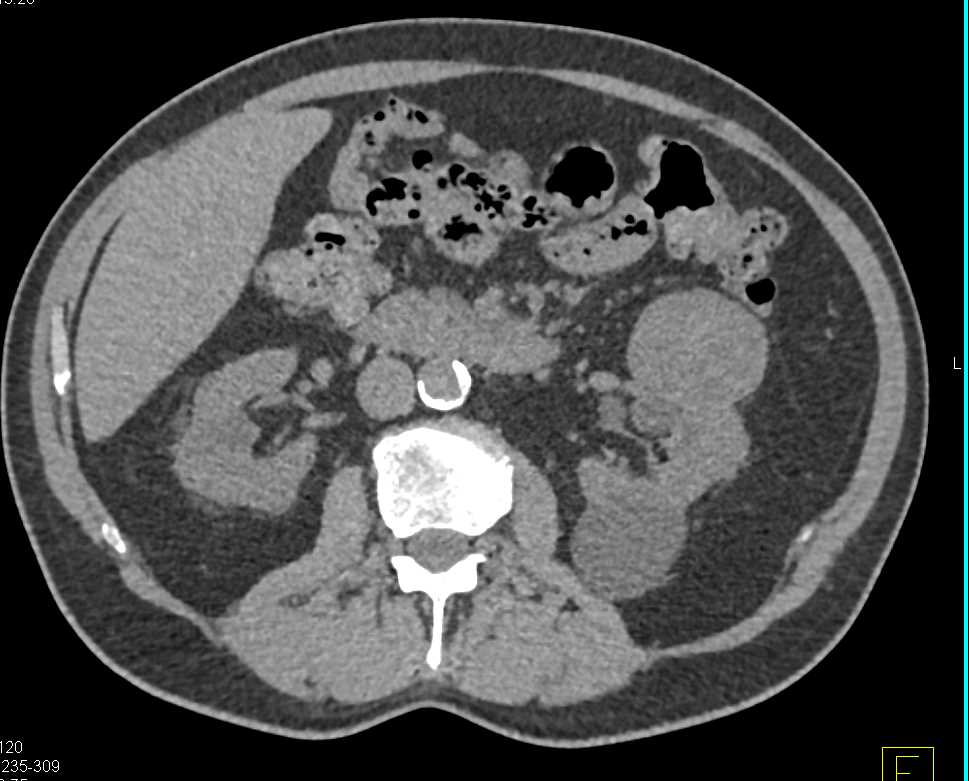

Abscess Lower Pole Right Kidney